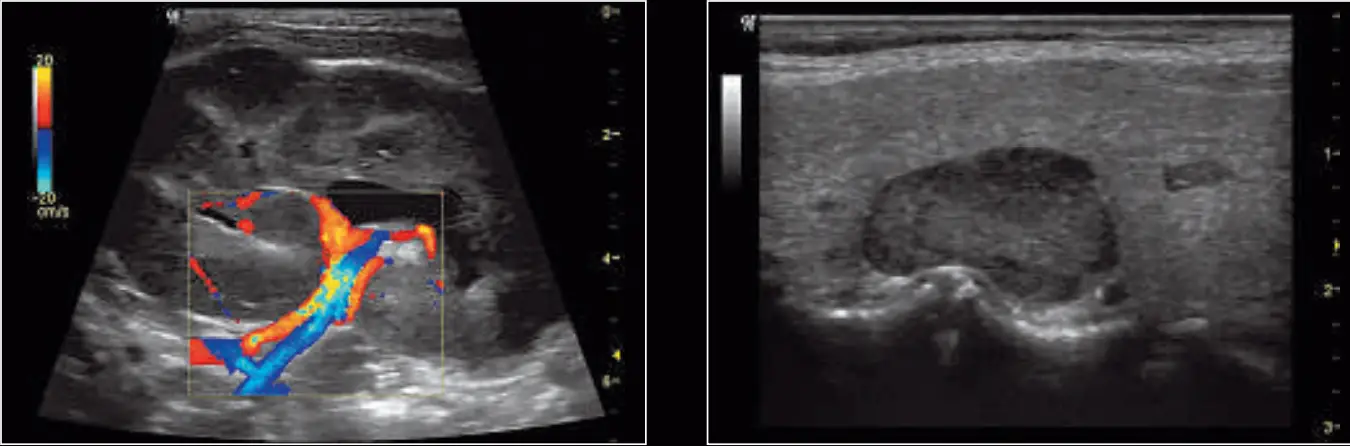

| Renal artery and vein displayed using the 11L probe and a combination of virtual convex, fundamental imaging, and SRI | High-frequency scan of parathyroid and irregular thyroid tissue; Phase Inversion Harmonics and SRI used to show maximum homogeneity and detail resolution |

| 11L sagittal vein with color Doppler using the 11L probe with Phase Inversion Harmonics, CrossXBeam, and SRI features | An internal carotid artery with color and pulse wave Doppler using the 11L probe with Coded Harmonics, CrossXBeam and SRI |